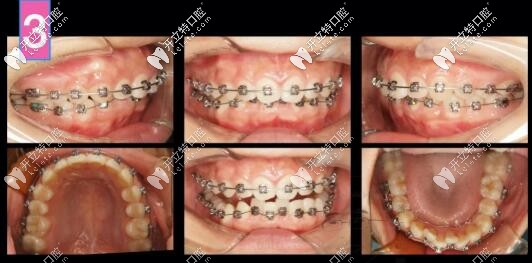

凸嘴自鎖托槽矯正案例

第6個月,上下都排齊了,下頜還是沒有主動跑出來,此時詞用支抗釘整體上牙內(nèi)收再看看

凸嘴支抗釘內(nèi)收

到了第八個月,嘴更凸了,因為上前牙恢復(fù)直立于牙槽骨中,凸度增加,臉頰還凹了,

因為下前牙唇傾出去,磨牙伸長,深覆合解決,下頜平面角加大

正畸拔牙

此時再來看看是否能拔牙

兩項指標(biāo)變了,可以拔牙,

治療計劃更新:拔上4下5,左側(cè)維持關(guān)系,拔上4下4

齙牙深復(fù)合牙齒矯正案例

前牙區(qū)支抗釘安排上!

矯正到34個月,姑娘終于露出久違的燦爛!